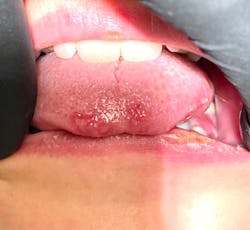

This 12-year-old presented with his mom for a dental visit. The chief complaint was that he was not feeling well, his mouth hurt, he couldn’t eat, it was painful to swallow, and he’d missed out on the last week of school. In general, his health history was unremarkable, temp was low-grade (99.8), and despite not being 100%, he was a trouper. Fist bumps, kiddo.

Note: The pictures are not of the highest quality as the patient was in extreme discomfort when I took them.

Definitive diagnosis is likely one of two: Herpangina or acute primary herpetic gingivostomatitis

The saying “nothing is for certain unless it’s in a petri dish” stands true in all pathology cases, including this one. However, based on the symptoms and clinical presentation, I was able to surmise that it was more than likely either herpangina or APHG, although I’m leaning toward APHG.